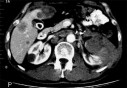

Une caravane médicale pour le dépistage des maladies chroniques a entamé ses activités dans la wilaya d’El-Bayadh, par des consultations à la polyclinique Lazari au chef lieu de wilaya, a-t-on appris jeudi des organisateurs.

Cette caravane, organisée sous l’égide du ministère de la Santé, de la Population et de la Réforme hospitalière, sous le signe de "La voie de la prévention", vise  à mener, durant une semaine, des actions de dépistage de nouveaux cas d’atteintes de maladies chroniques, ainsi que le suivi des cas de complications chez des diabétiques et hypertendus, a indiqué à l’APS la chargée du suivi du programme national de lutte contre le diabète au niveau du ministère, Dr. Halima Imami.

Cette caravane médicale renferme plusieurs spécialités liées à l’ophtalmologie, la cardiologie les maladies cardiovasculaires, la médecine générale et les analyses médicales, a-t-on signalé.